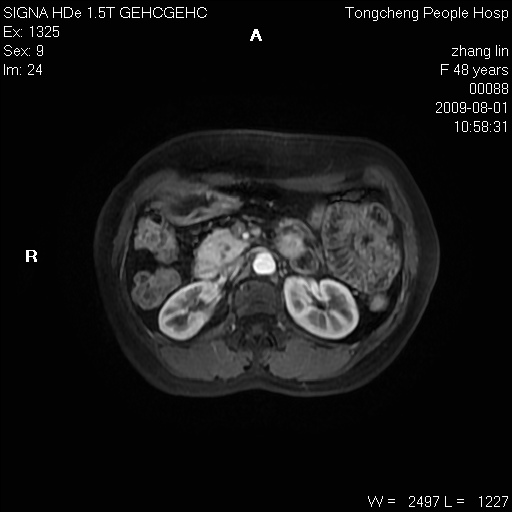

女,48岁。健康体检,彩超发现右肾占位性病变。平素健康。

临床诊断:右肾占位性病变,性质待定(囊肿?肿瘤?)。

上中腹部mr平扫+增强扫描,图像如下:

右肾上极见一类圆形病灶,t1wi呈等信号t2wi呈等高混杂信号,三期增强无强化,边界清---考虑囊肿出血。

同反相位均表现为等信号,病变无强化,考虑含蛋白的囊肿可能,弥散加权相或许有些帮助,

慢性胆囊炎